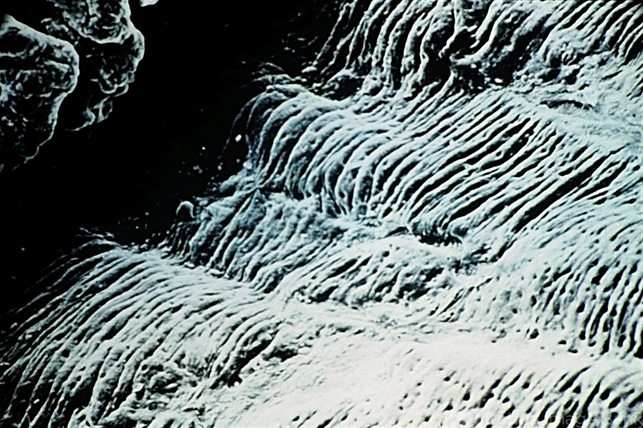

- Pigmentary glaucoma. Scanning electron microscopic appearance of the back of the iris, showing loss (flattening) of the circumferential ridges of the posterior iris at the sites of involvement (SEM x50).